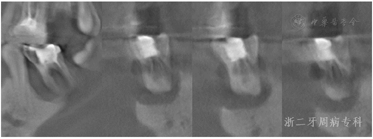

2020年11月:牙周基础治疗后12年复诊,行牙周检查和疗效评定。患者牙周状况较上一次复诊好转,牙周袋进一步变浅,全口BOP(+)%降低到18.5%,但36近中颊侧与舌侧两个位点均探及10 mm深的牙周袋(表6)。予牙周维护治疗,强化口腔卫生指导,嘱定期牙周复诊。因患者口内多牙楔状缺损,14近中颈部、27颊侧龋坏,患者仍未充填治疗,再次提醒患者尽早充填治疗。

2021年8月:牙周基础治疗后13年复诊,患者口腔卫生维护佳,牙周状况较上一次复诊牙龈色粉,无明显红肿,口内下前牙区可见少量龈上结石(图23),松动度进一步改善,全口BOP(+)%进一步下降至15.4%,但36仍可探及较深牙周袋,近中探诊能触及根尖(图24)。X线片示:与2018年12月比较,36近中根牙槽骨进一步吸收,吸收已达根尖,而全口其余位点牙槽骨没有明显出现进一步吸收现象;14根尖可见低密度影(图25)。口腔锥形束CT(CBCT)示:36近中根牙槽骨吸收至根尖,牙齿与骨面基本分离,舌侧骨壁缺失,颊侧骨壁较低(图26)。本次行复发危险评估结果示高复发危险度,但与上次评估相比,由3个高度危险因素转变成2个高度与1个中度,情况有所好转(图27)。